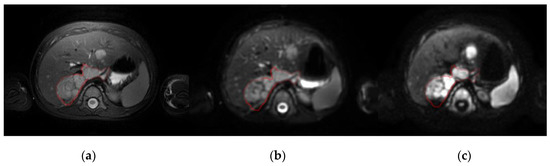

Figure 4.

Parametric (left) and representative (right) maps of the apparent diffusion coefficient (ADC) in the voxel-based, cluster-based and Fit-Cluster-Fit models at different confidence thresholds for uncertainty exclusion (60%, 70%, 80%, 90% and 95%). The ranges established were: parametric maps, red (0.5·10−3 mm2/s)–blue (3.0·10−3 mm2/s); and representative maps, yellow (lower ADC habitat)–green (higher ADC habitat).

Representative maps for the ADC values in the voxel-based, cluster-based and Fit-Cluster-Fit models are shown in Figure 4 for the different confidence thresholds to exclude uncertainties (60%, 70%, 80%, 90% and 95%). Those voxels with low ADC values in the parametric map were mostly assigned to the lower ADC habitat in the respective representative maps. As the exclusion threshold increased, more high-uncertainty voxels were removed from their corresponding cluster, with the extreme scenario of encountering a few low-uncertainty voxels belonging to the most aggressive habitat.